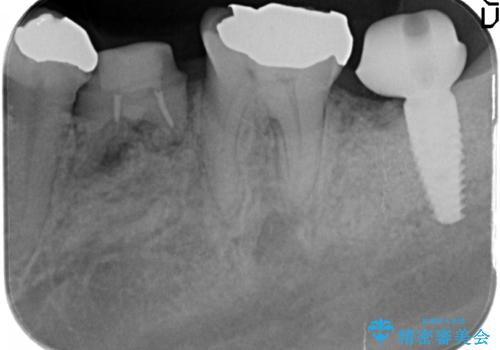

今後の機能回復方法としてインプラント治療を希望されたため、将来的に大規模な骨造成が必要とならないよう歯槽堤保存術を抜歯と同時に行いました。

良好なインプラントの植立を行うためには、十分な骨量があることが必須条件です。

術前、歯の破折により大きな骨の吸収が認められていたため骨量を十分に回復するために抜歯と同時に歯槽堤保存術を行い十分な骨量の回復をすることができました。